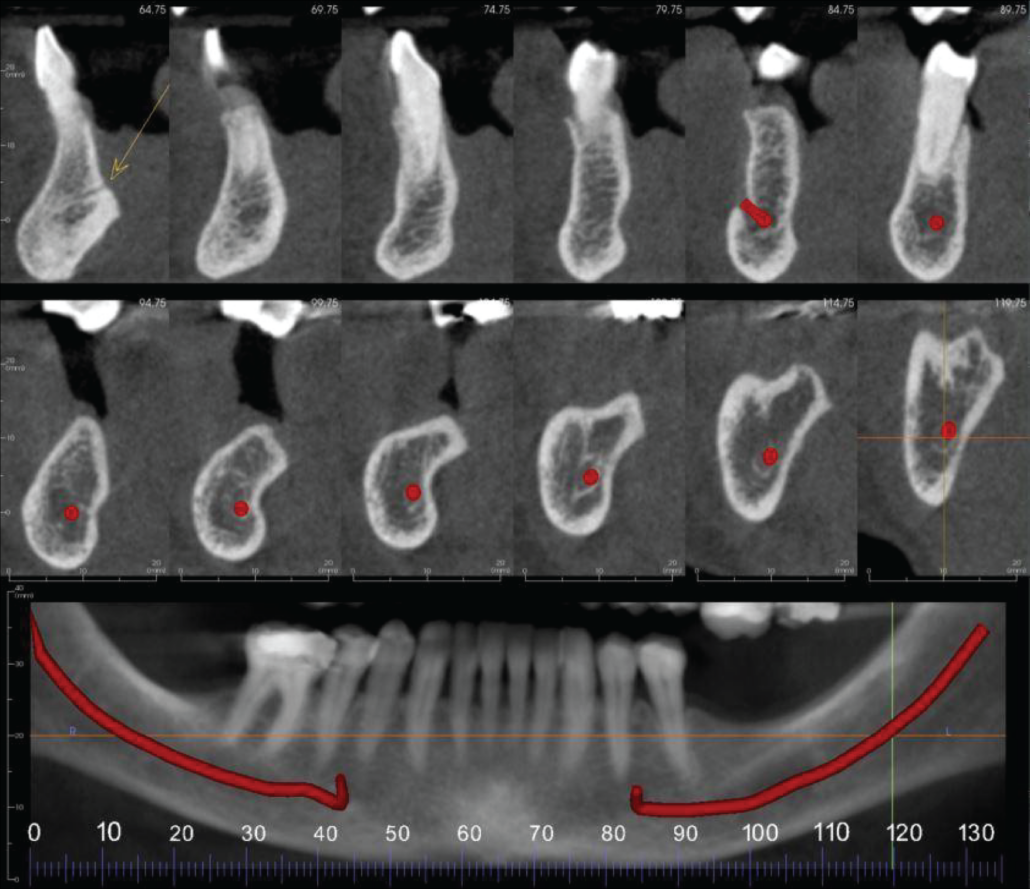

Cropped panoramic and cross sections of the UR8-4 region. The UR8-6 has severe loss in vertical alveolar ridge height. The UR6 region has erosion of the maxillary sinus cortical floor and alveolar ridge (circled). The UR5 has widening of the apical periodontal ligament space (arrow).